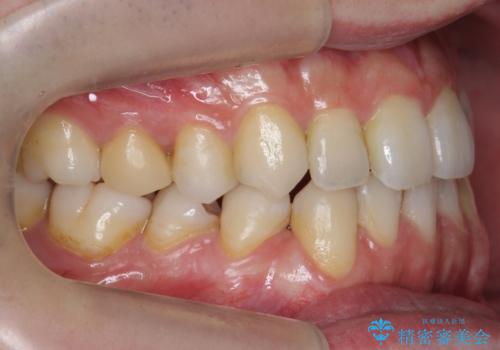

前歯の矮小歯 奥歯の反対咬合 をインビザラインで

- 上下の前歯が気になり来院。

左上2が矮小歯で小さく、また、左の奥歯が反対咬合になっていました。

左上2番はセラミッククラウンで反対側と同じ大きさにしました。

インビザラインでの臼歯の反対咬合の治療は難しいことが多いです。

今回は下の前歯を1本抜くことで、下の奥歯をしっかり内側に傾けて治療を行いました。